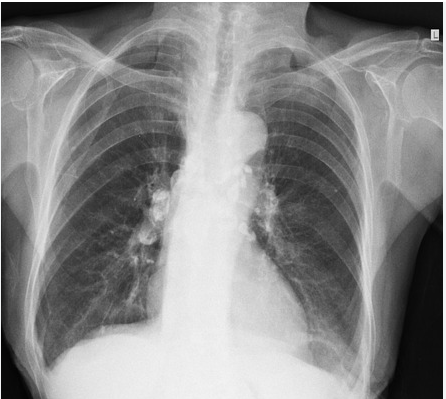

28

principal acometimento radiográfico da TB pós-primária

normalmente envolve os segmentos apical e posterior dos lobos superiores

29

manifestação radiográfica mais comum na TB pós-primária

áreas irregulares de consolidação com margens mal definidas